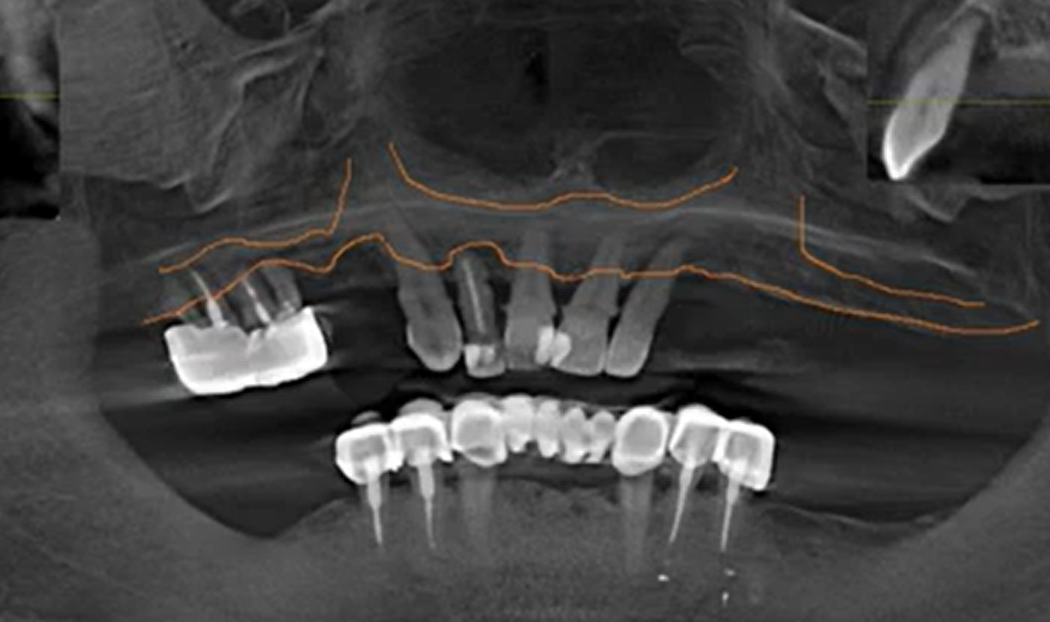

An example of a clinical situation with hopeless teeth and bone deficiency. The Full-Arch on 4/6 protocol helps avoid risky bone augmentation surgeries. YouTube/ Dr. Sergey Rozhnov /sergiodontologist

Consider a patient with severe periodontitis, mobile teeth, and significant bone loss in the maxilla. A classic (delayed) protocol would require multiple bone grafting surgeries, each carrying specific risks. While a restoration supported by 8–10 implants is often considered more “reliable” (as it eliminates cantilevers and allows the arch to be divided into segments), the Full-Arch on 4/6 protocol offers a streamlined alternative. In this protocol, the arch typically ends at the first molars, often utilizing distal cantilevers.

- Bone volume and density analysis.This is important for choosing the correct positions for implant placement. Most often, patients have bone defects, a thin alveolar ridge, irregularities, cysts, etc. A typical picture is a height difference between the anterior and posterior jaws. Typically, the anterior teeth in both jaws last longer, and the alveolar ridge is higher than in the posterior jaws.

Conventionally, three zones of analysis can be distinguished, see the picture below:

The image above shows an uneven alveolar ridge in the anterior region, as well as a noticeable bone deficiency in the masticatory zone of the first quadrant. This means that after tooth extraction, a bone reduction in the anterior region will be necessary.

The image above shows a typical scenario. Preliminary analysis is critical for protocols with a limited number of implants.